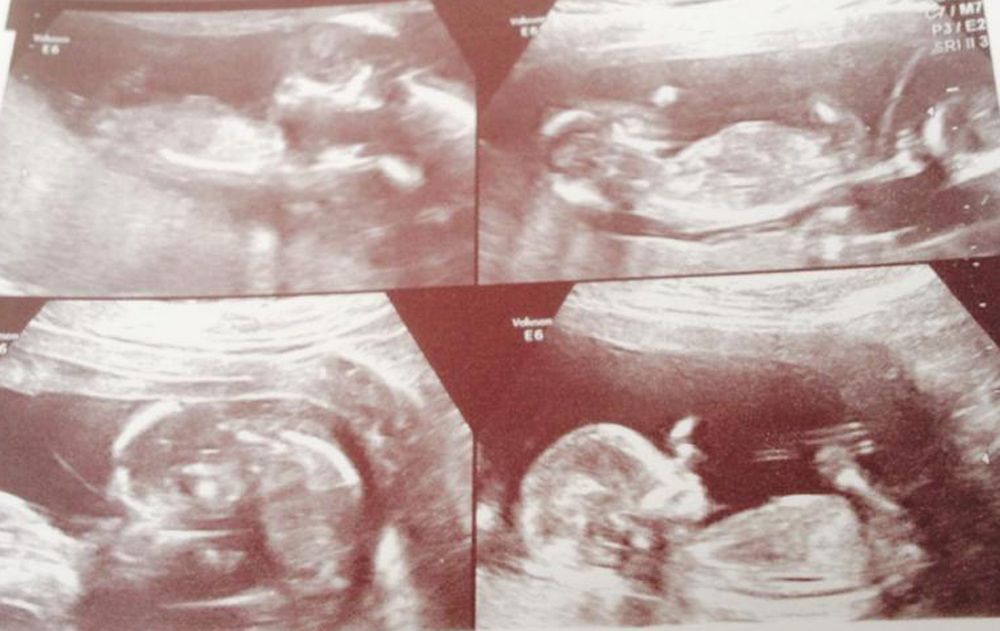

Six weeks later, at her 12-week scan, Tracy discovered that she was not having twins, but quadruplets.

“As the sonographer moved the ultrasound wand over one of the sacs, they saw two little flutters – two heartbeats."

“When they checked the other sac, the same thing happened. The doctor's jaw hit the floor as he turned and said, 'You're having quadruplets.'"

They discovered that, while one of the three embryos had not taken, the remaining two had both split, meaning Tracy was carrying two sets of identical twins.

According to a professor of obstetrics, gynecology and reproductive biology at Harvard Medical School, the odds of that happening are one in 70 million.